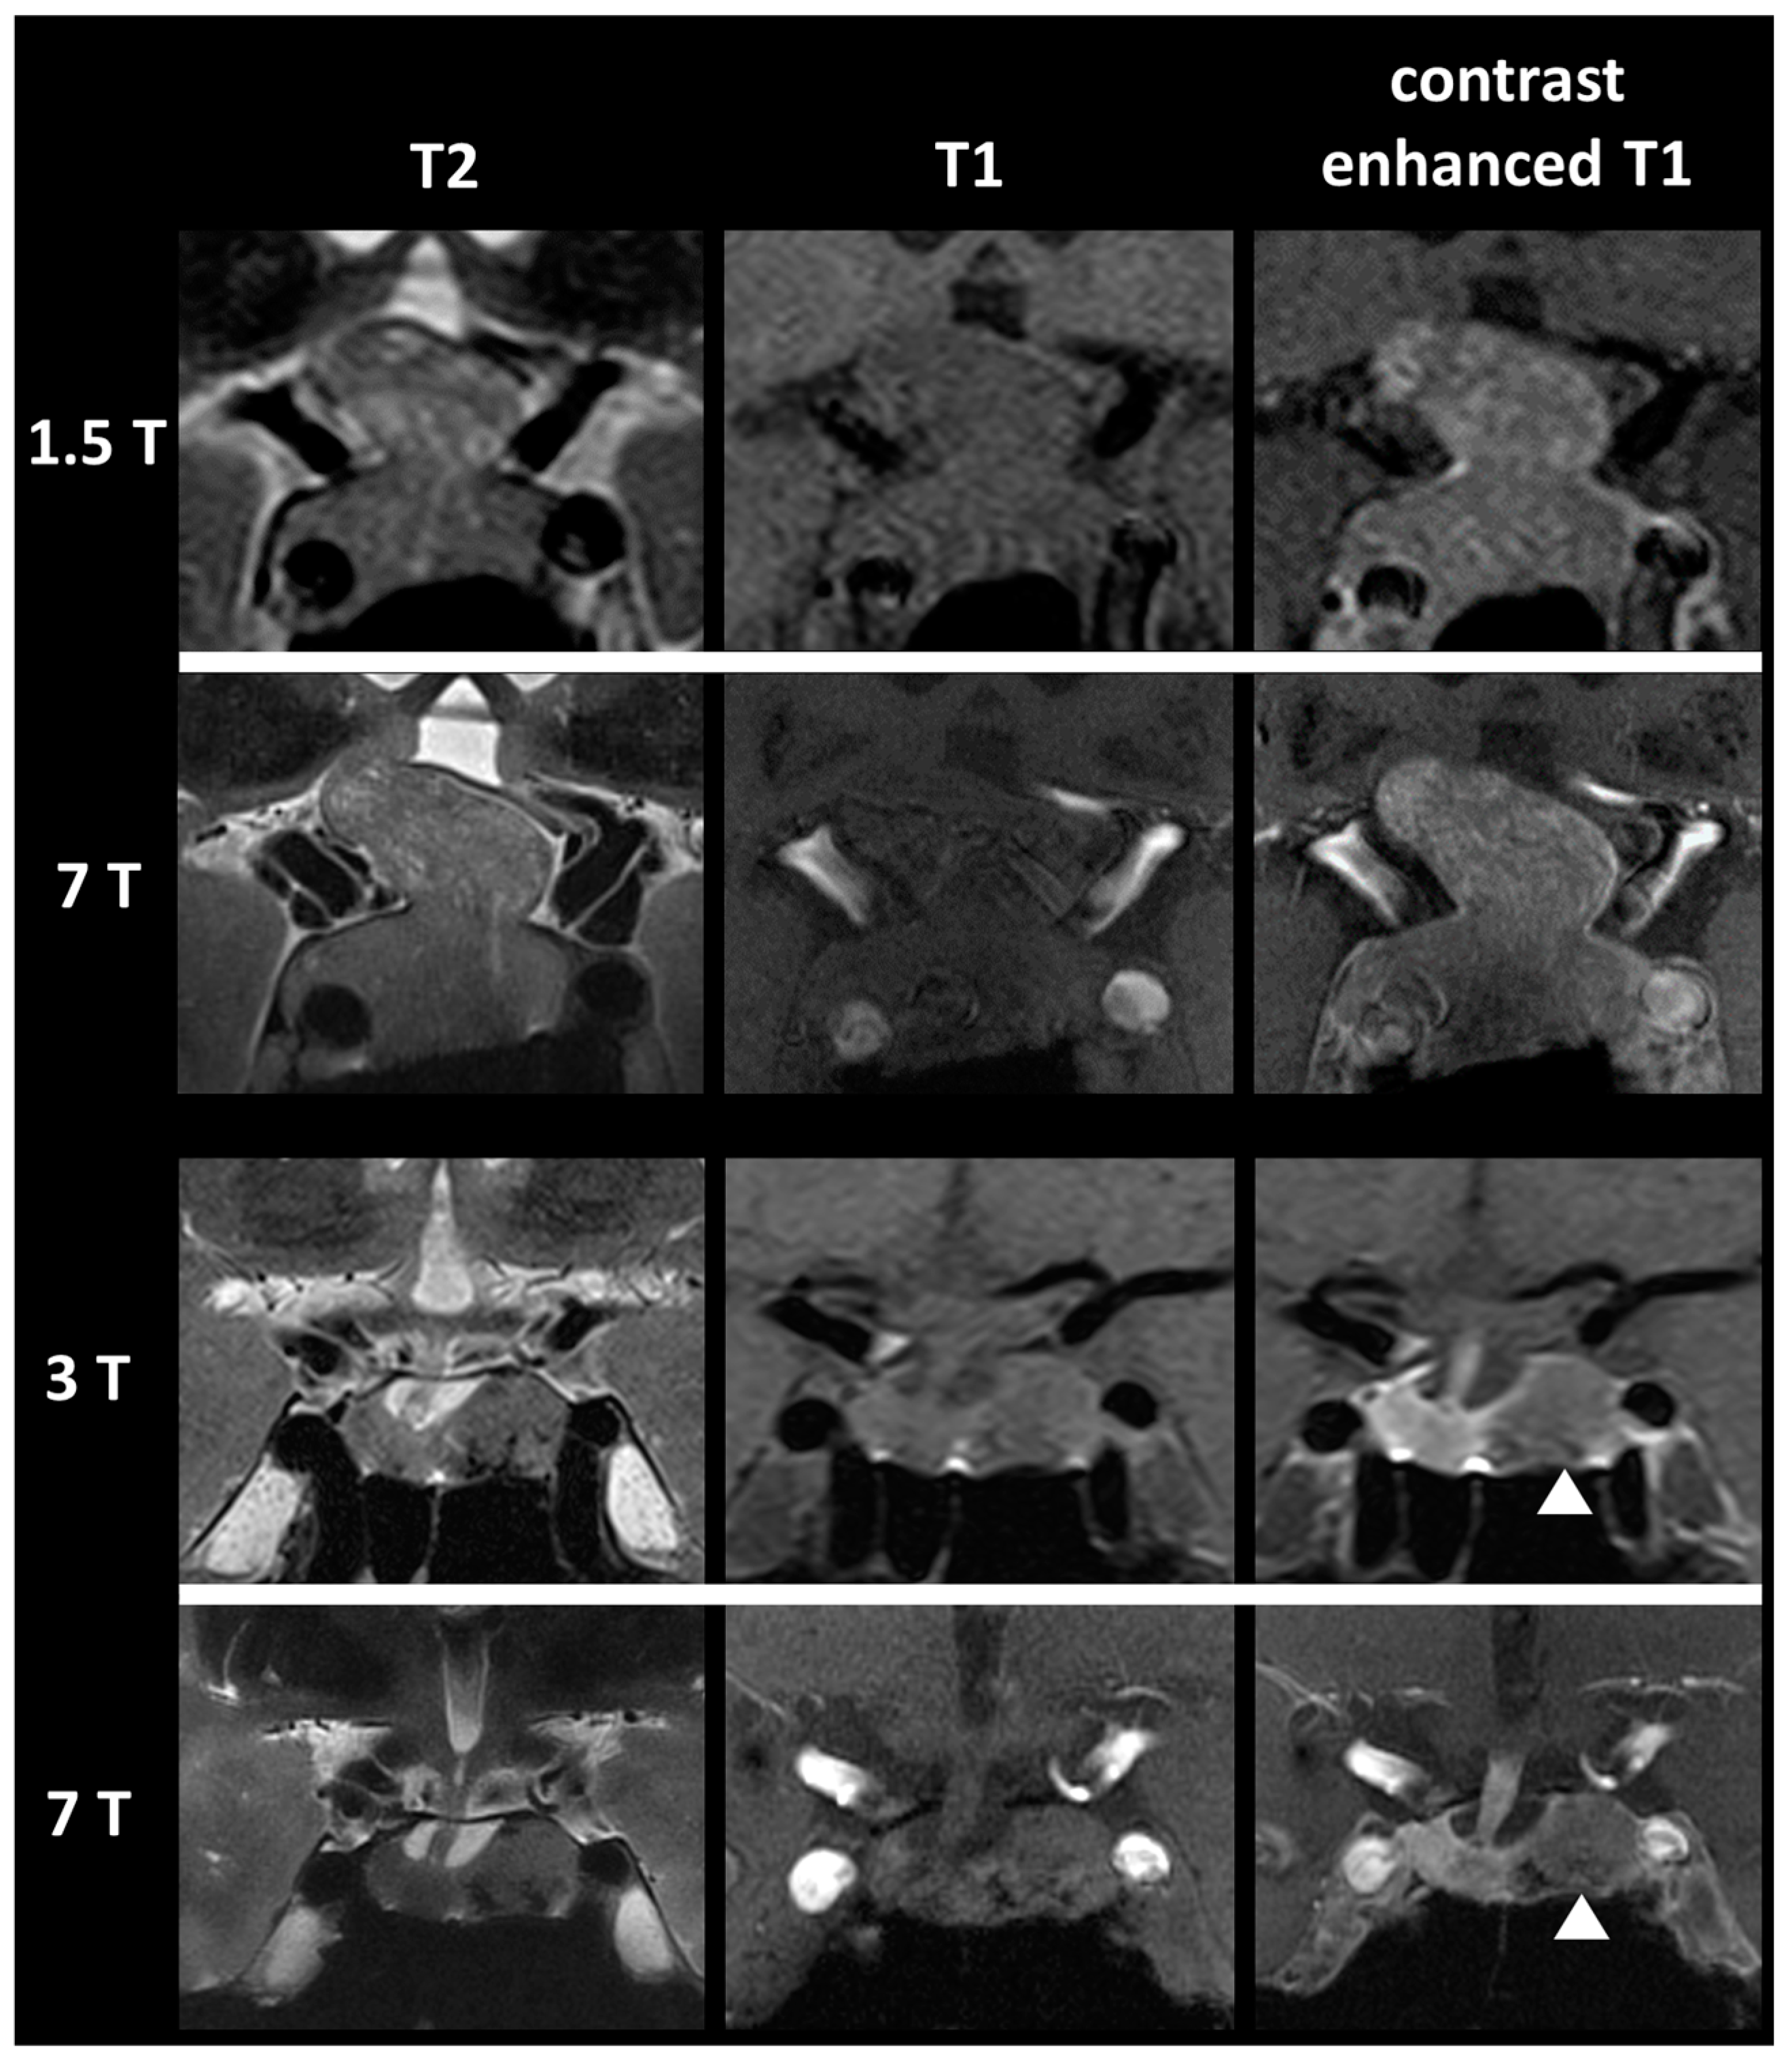

Improved Detection of Cavernous Sinus Invasion of Pituitary Macroadenomas with Ultra-High-Field 7 T MRI